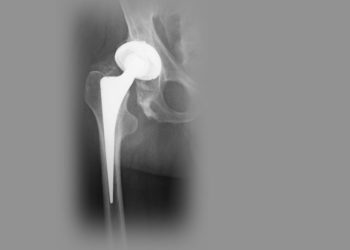

Die nächste Samstags-Klinik des Elbe-Elster Klinikums beschäftigt sich am 23. April in Elsterwerda mit dem Thema „Künstliches Hüftgelenk – Fluch...